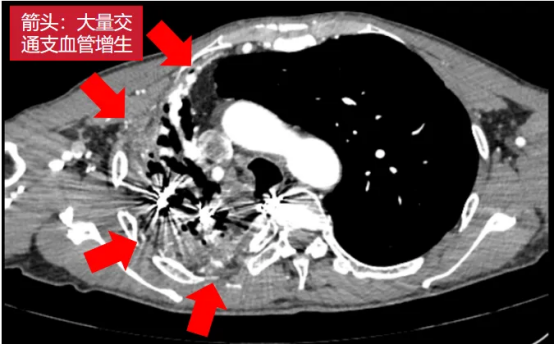

术前影像(左右滑动查看更多)

该患者为61岁男性,肺部病情错综复杂。4年前确诊肺结核后因治疗不规范,发展为“利福平耐药”结核,病情持续恶化。2年来反复咯血,虽经3次支气管动脉栓塞术暂时控制,但病灶顽固,收治入院时已形成多重诊断:毁损肺(右上)、右肺下叶鳞癌(背段)、肺曲霉菌病、陈旧性肺结核。其右肺上叶完全丧失功能,并与胸壁形成致密粘连,医学上称为“毁损肺”——胸外科领域公认的极高难度手术。

手术如期进行,然而打开胸腔的瞬间,其严峻程度远超预期:胸腔呈广泛致密黏连、完全闭锁,右肺上叶仿佛被水泥浇筑在胸壁上;肺表面及壁层胸膜布满大量脆弱的新生血管,呈现出“碰一下就出血”的凶险局面。